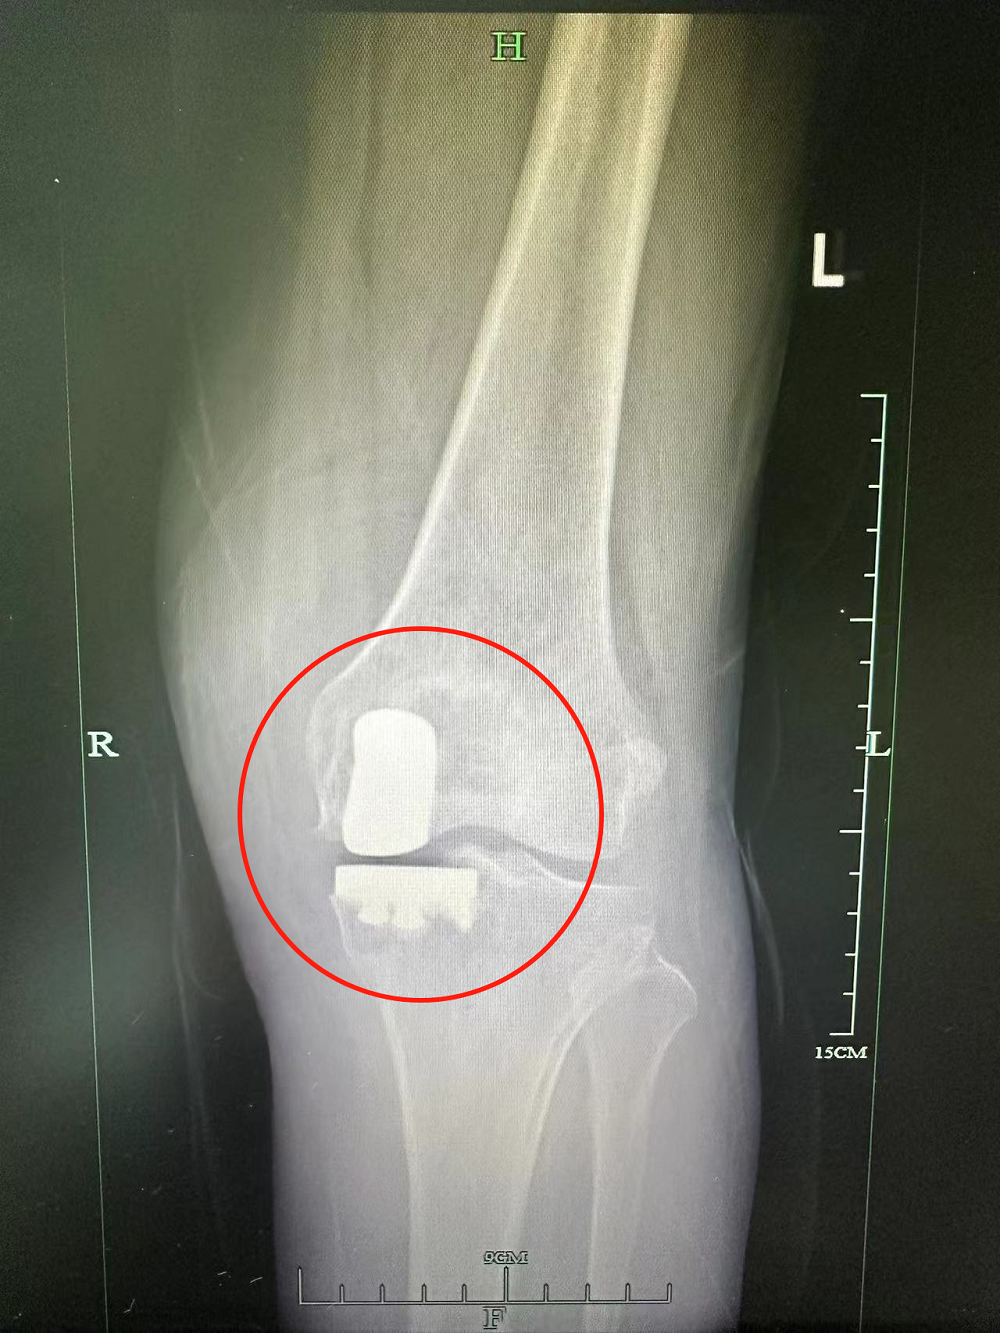

近日,新昌县人民医院创伤骨科成功为一名股骨髁骨坏死的老年患者开展微创膝关节单髁置换术,术后第二天患者便能下地行走,康复效果良好。 72岁的姚阿姨,左膝关节不适一年余,正常行走越来越吃力。曾多次就医,医生建议其行关..